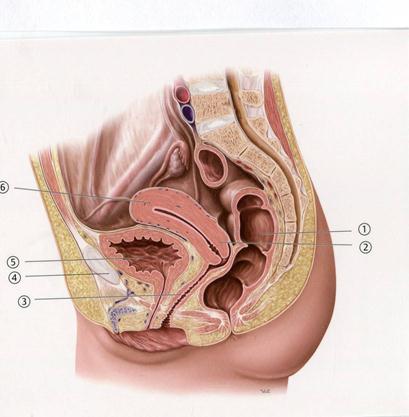

+A. Жатыр

B. Жатыр- тік ішек кеңістігі

C. Несеп қуық

D. Тоқ ішек

E. Тік ішек

+D.Мойын өзегі

А.Жатыр

В.Қасаға симфизі

С.Қынап

+D.Несеп қуық

Е.Тік ішек